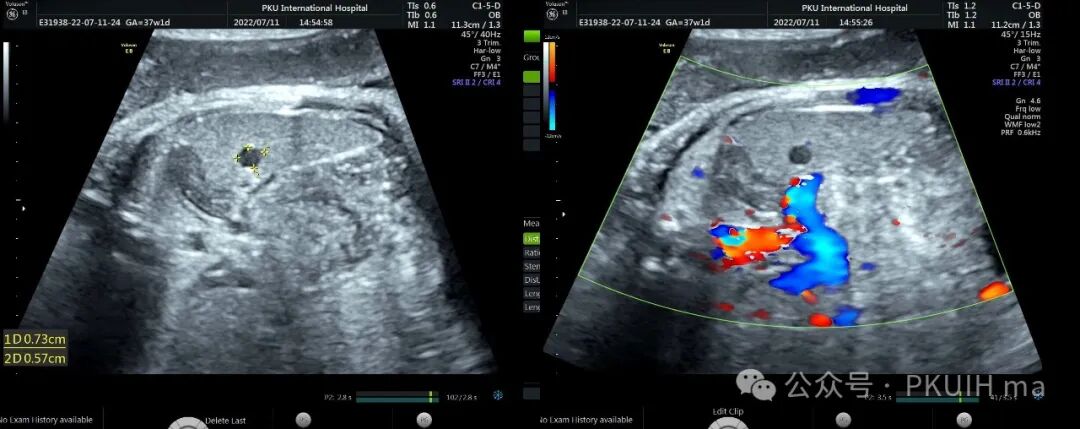

上两张图(第二张是37周)是一例在30周发现的肝囊肿,在随后观察中囊肿一直无变化